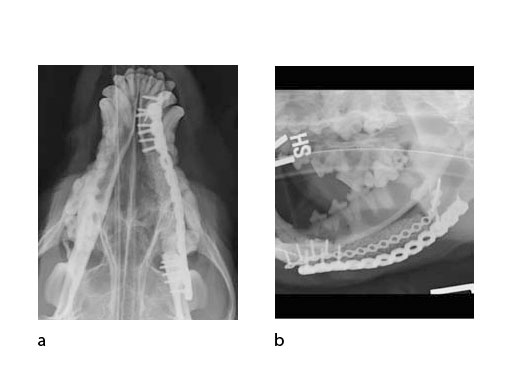

A block of compressive resistant matrix (CRM) was cut to fill this bone void, which was soaked with 2 mg of rhBMP-2. Fig 4 shows an intraoperative view of the 2 plates secured to the mandible and the CRM in place within the bone defect. The soft tissues were closed routinely. Immediate postoperative x-rays show the fixation (ventrodorsal view and lateral oblique view) (Fig 5). The radiopaque CRM can be observed spanning the 5 cm defect.

Follow-up x-rays at 7 months postoperatively (ventrodorsal view and lateral oblique view) (Fig 6) show healing of the defect (and resorption of the CRM), which was documented with a Jamshidi biopsy of the center of the original gap (Fig 7). The biopsy was performed at the same time as partial plate removal (Mini Plate) due to the intraoral plate exposure.